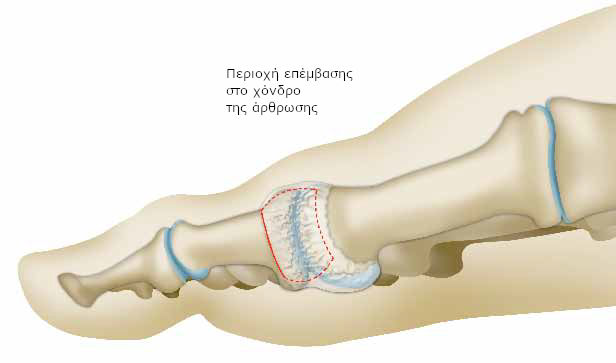

Εάν ο χόνδρος είναι ιδιαίτερα φθαρμένος, ή εάν τα οστά είναι ιδιαίτερα κοντά, ο χειρουργός προχωρεί σε αρθροπλαστική.

Αρχικά, πραγματοποιεί τομή στον ινώδη σάκο που περιβάλλει την άρθρωση (αρθρικός θύλακος) σε συγκεκριμένο σημείο.

Αφαιρεί, στη συνέχεια, το φθαρμένο χόνδρο της φάλαγγας και καθαρίζει το οστό από προεξοχές.

Τέλος, τοποθετεί και συρράφει το θύλακο με τέτοιο τρόπο, ώστε να αντικαθιστά το φθαρμένο χόνδρο.

Δημιουργείται, με αυτό τον τρόπο, ένα είδος τεχνητής άρθρωσης.